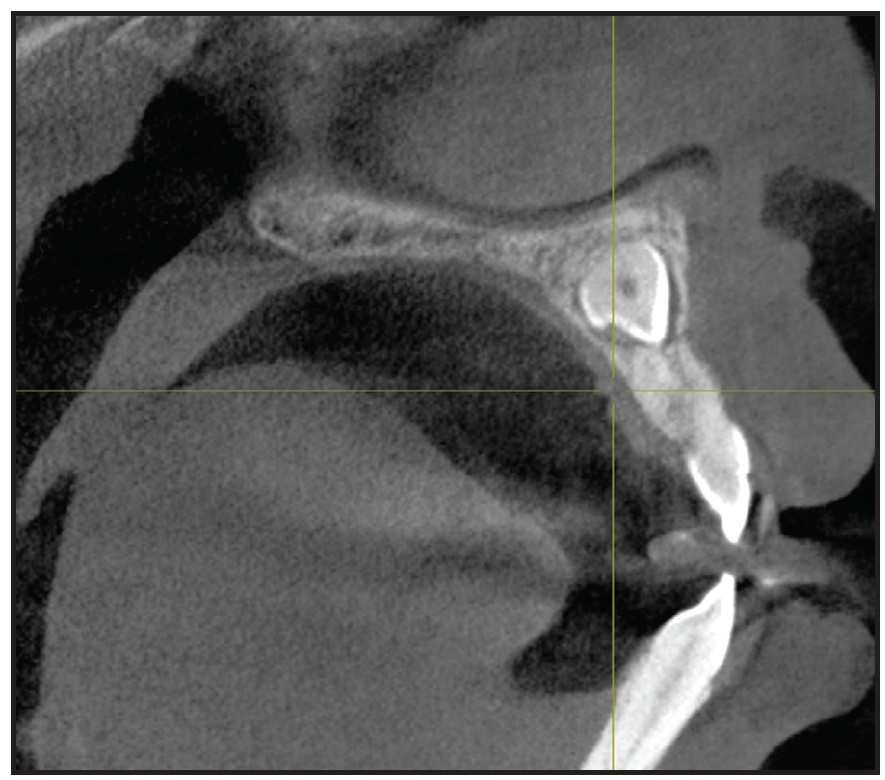

The panoramic radiograph revealed impacted upper permanent canines, a horizontally impacted lower right third molar, and an unrestorable lower right first permanent molar. Sagittal cone-beam computed tomography (CBCT) of the upper arch located the impacted canines near the upper midline, past the apex of the upper central incisors (Fig. 2).

Fig. 2 Impacted upper canines visible on sagittal cone-beam computed tomography.